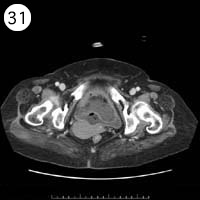

31

57歳 女性